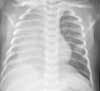

Figure 2

A follow-up chest film was ordered (Figure 2). Findings were interpreted as significant progression of right pulmonary parenchymal disease, with likely pneumonia involving the right upper, middle, and lower lobes. Because of his acute clinical deterioration, the patient was given intravenous vancomycin pending final susceptibilities.